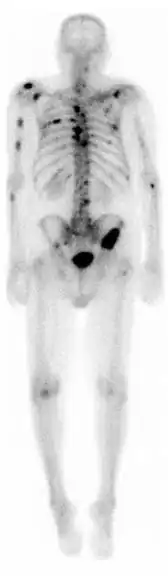

Gammagrafía ósea

Una gammagrafía ósea es una prueba de medicina nuclear para encontrar ciertas anormalidades en los huesos. Se utiliza sobre todo para ayudar a diagnosticar: cáncer de los huesos o cáncer que se ha diseminado (metástasis) hasta el hueso, la localización de algunas fuentes de inflamación en los testículos (por ejemplo, dolor óseo, tales como dolor de espalda debido a una fractura), el diagnóstico de las fracturas que pueden no ser visibles en las tradicionales imágenes de rayos X, y la detección de daños en los huesos debido a ciertas infecciones y otros problemas.

En general, lo que se busca con esta prueba diagnostica son imágenes de hipercaptación que pueden ser localizadas, múltiples o difusas. Cuando son difusas recibe el nombre de superscan. Las imágenes de hipocaptación son más raras. El aumento de captación ósea puede ser por cuatro motivos: el aumento de la formación osteoide, una mineralización ósea aumentada, un aumento de la vascularización, del flujo sanguíneo, o por una denervación simpática.

Un dato importante a tener en cuenta es que no todas las imágenes de hipercaptación son patológicas, por eso es muy importante que la imagen la valore un médico. Por ejemplo, las áreas de hipercaptación simétricas en un niño en edad de crecimiento no son patológicas, sino que corresponden a los puntos donde se está formando el hueso, las epífisis

La técnica en sí consiste en la administración intravenosa de 10-20 milicurios de 99mTc-MDP (Metilén difosfonato) o de 99mTc-HEDP (Hidroxi-Etilén-difosfonato). Tras 2-5 horas postinyección se realiza la adquisición de las imágenes de cuerpo entero, que se llama rastreo anterior y rastreo posterior. Eventualmente, estos rastreos de cuerpo entero se pueden complementar con: gammagrafías localizadas de huesos concretos, SPECT muy útil en columna vertebral y pelvis o gammagrafía ósea de tres fases.